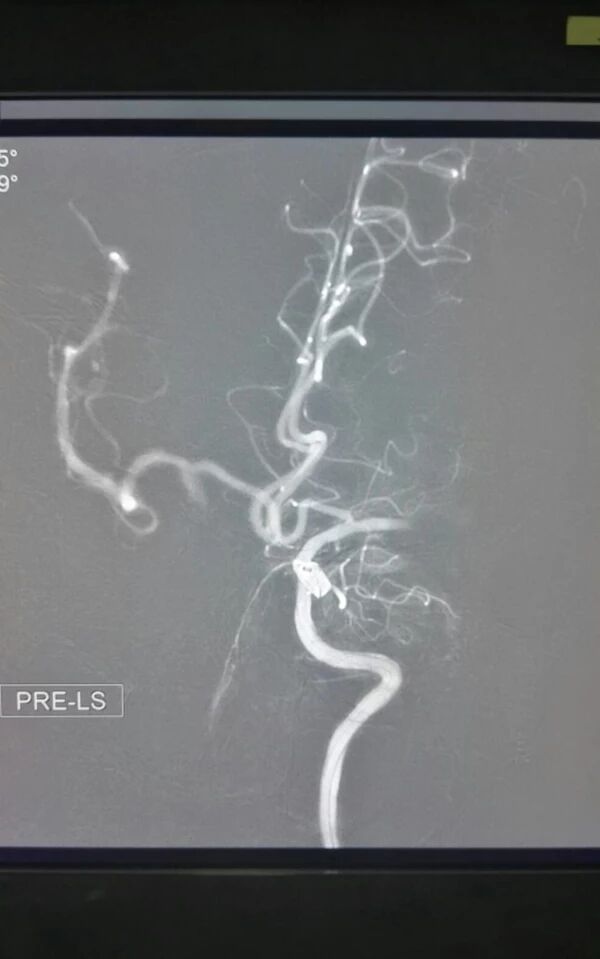

术前脑血管造影显示左侧大脑中动脉急性闭塞,代偿不佳

微导管通过血栓后造影显示远端血管通畅